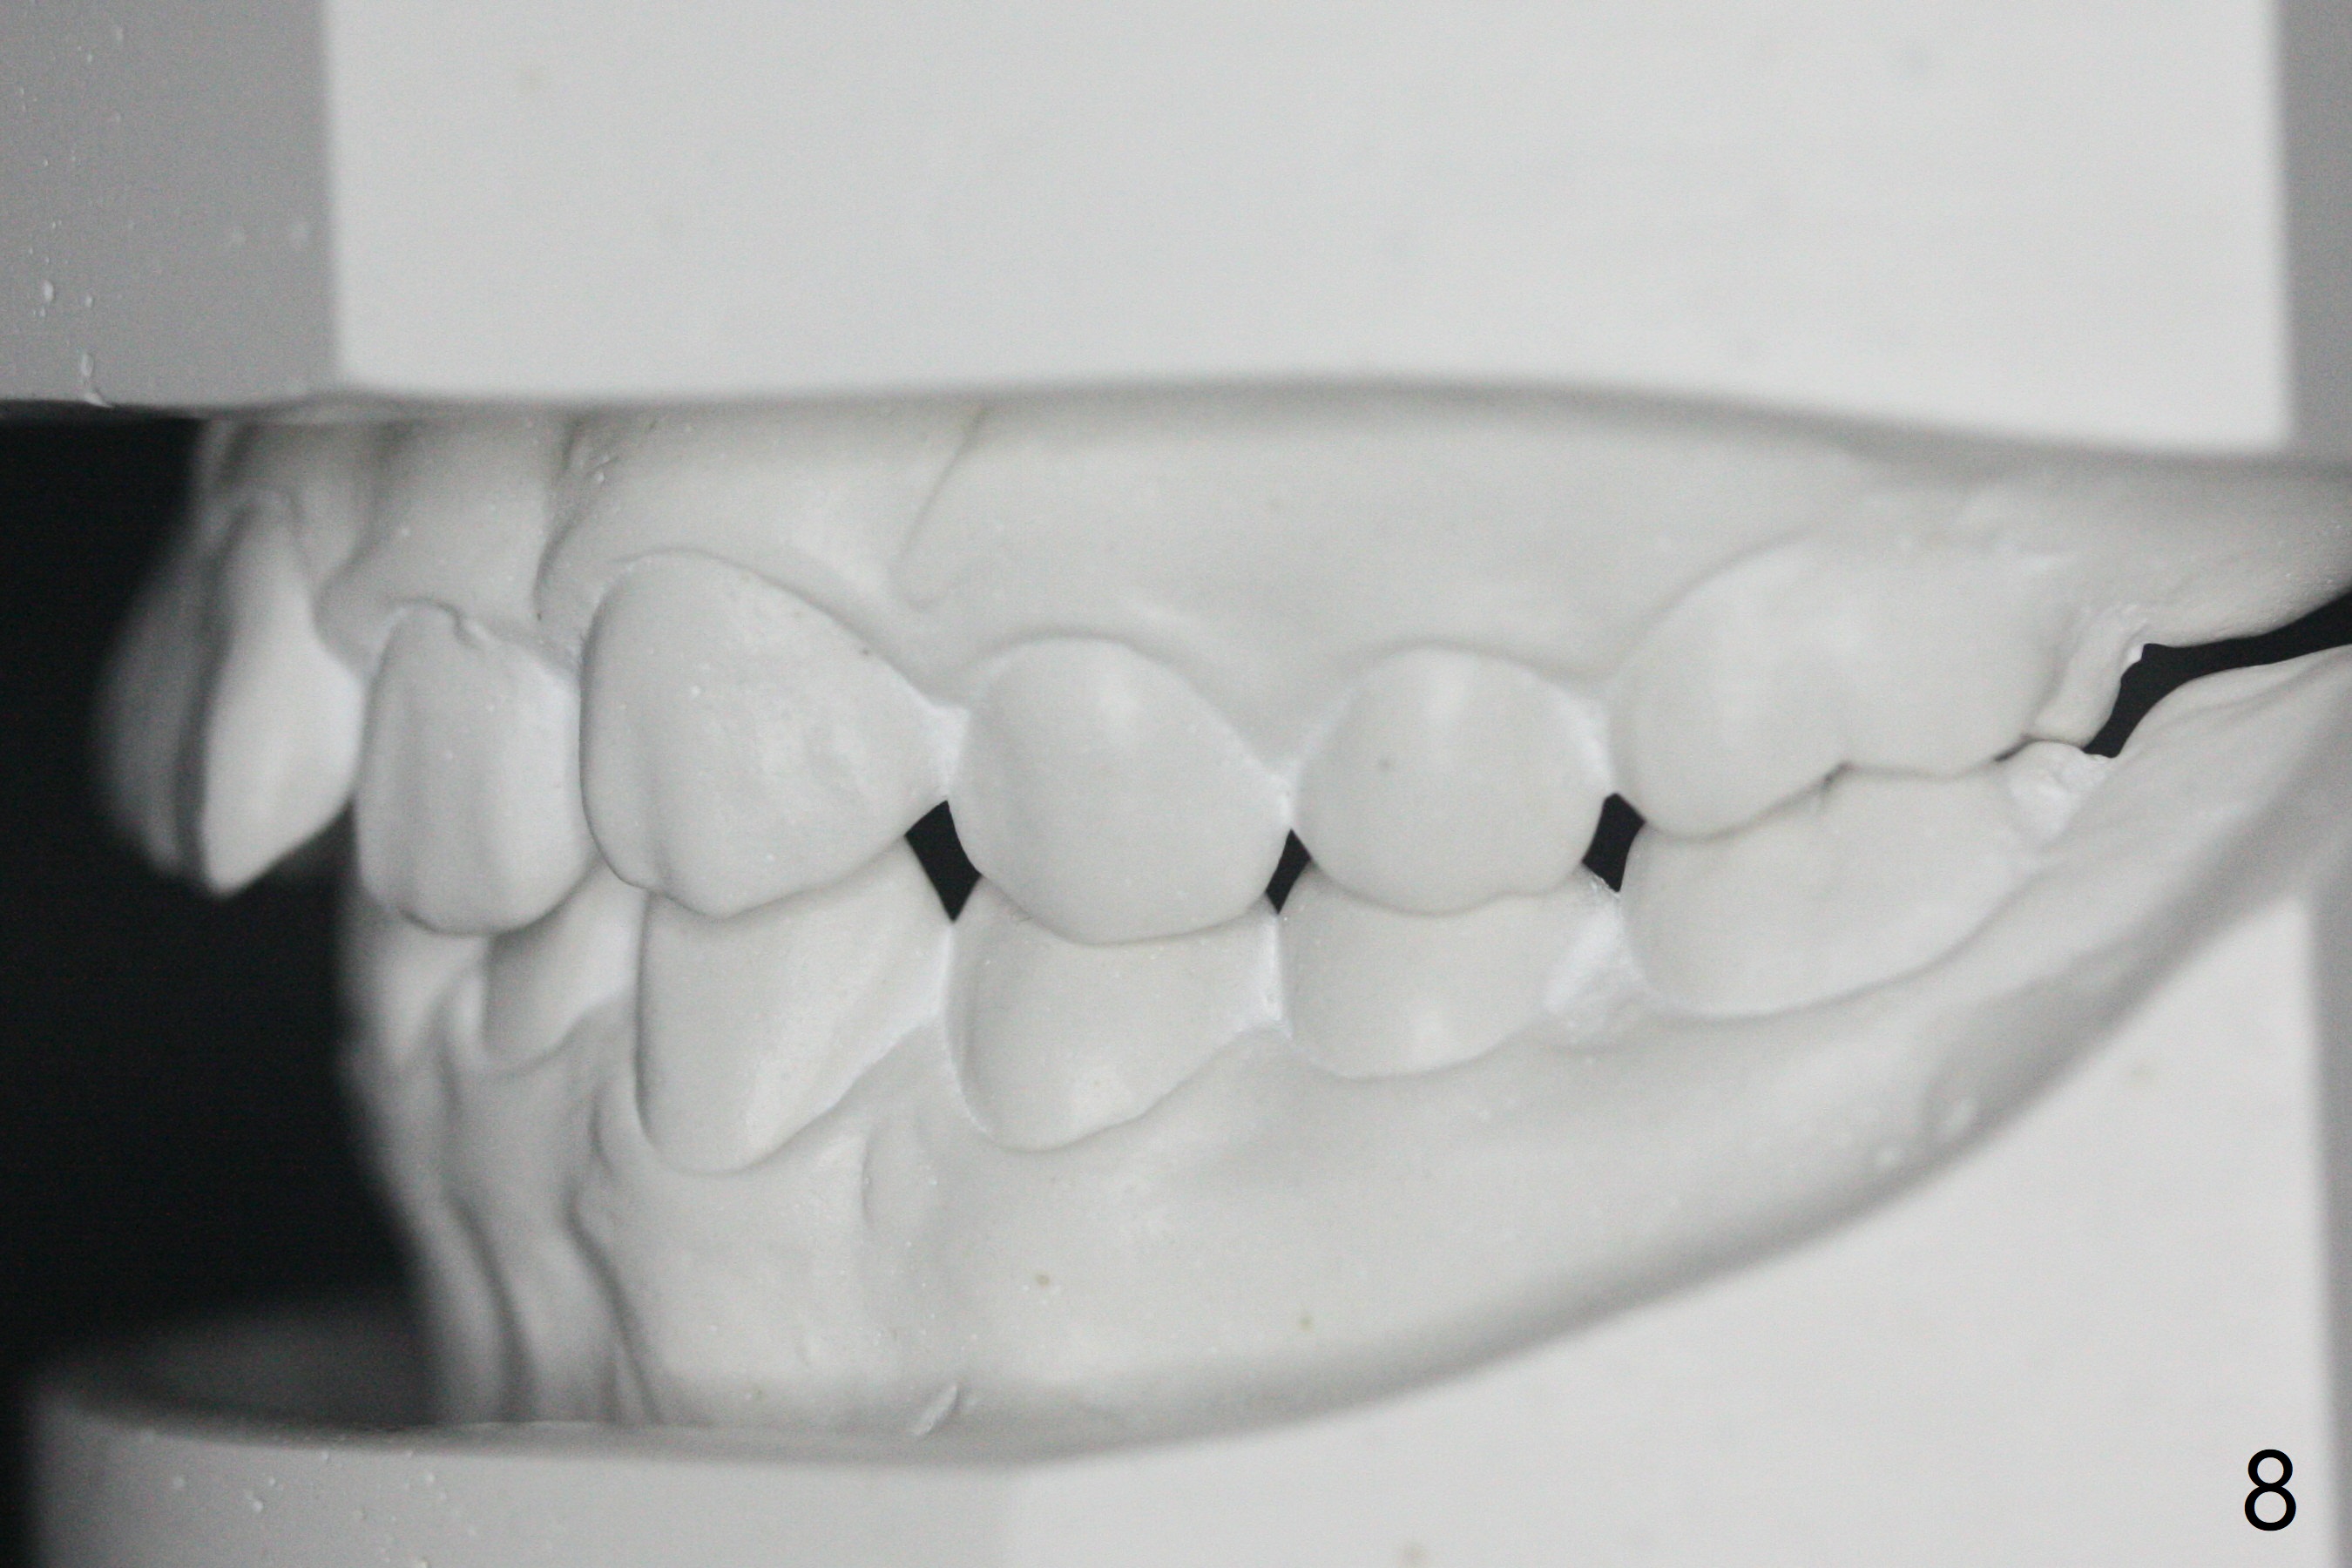

A 12-year-old woman has Class I facial profile (Fig.1-4,12,13) and apparently Class II Division I malocclusion (Fig.6-11). Start Class II retraction as early as possible to take advantage of the upper and lower posterior diastemata (Fig.9,11 (in fact there is no diastema)). LL7 impaction is noted immediately prebanding (Fig.14). Surgical access is pending.